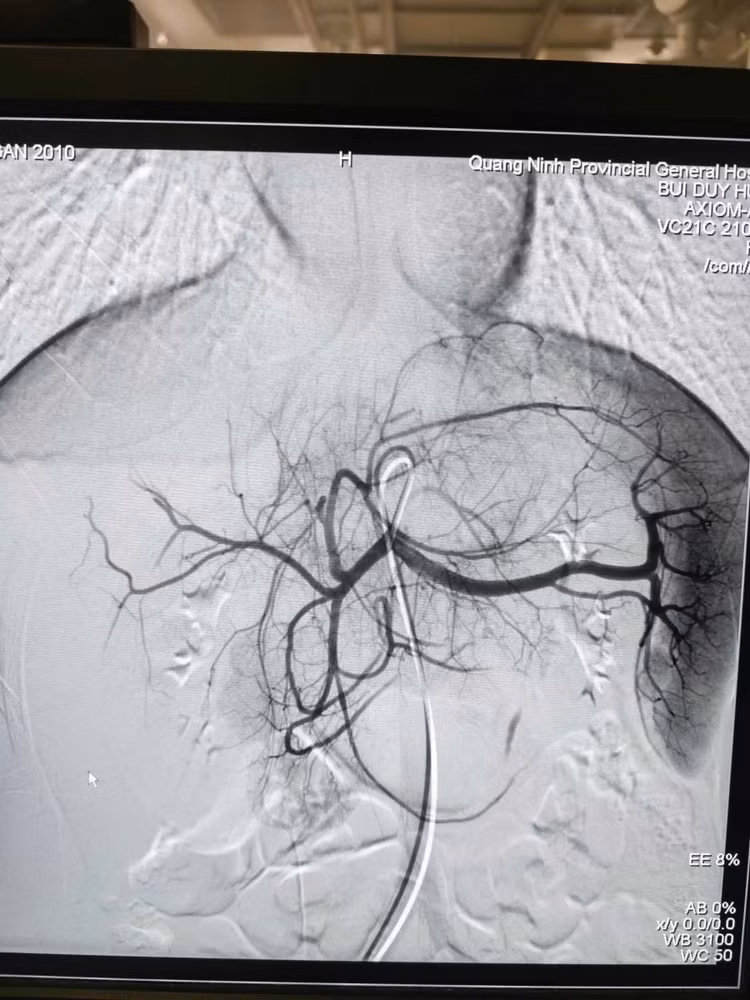

Hình ảnh sau nút mạch điều trị chấn thương gan, ổ chảy máu đã được nút tắc - Ảnh BVCC

Sau 60 phút, ca can thiệp thành công tốt đẹp, hình ảnh chụp kiểm tra cho thấy điểm chảy máu đã được cầm hoàn toàn. Huyết động bệnh nhân ổn định và được chuyển hậu phẫu theo dõi với tiên lượng phục hồi.